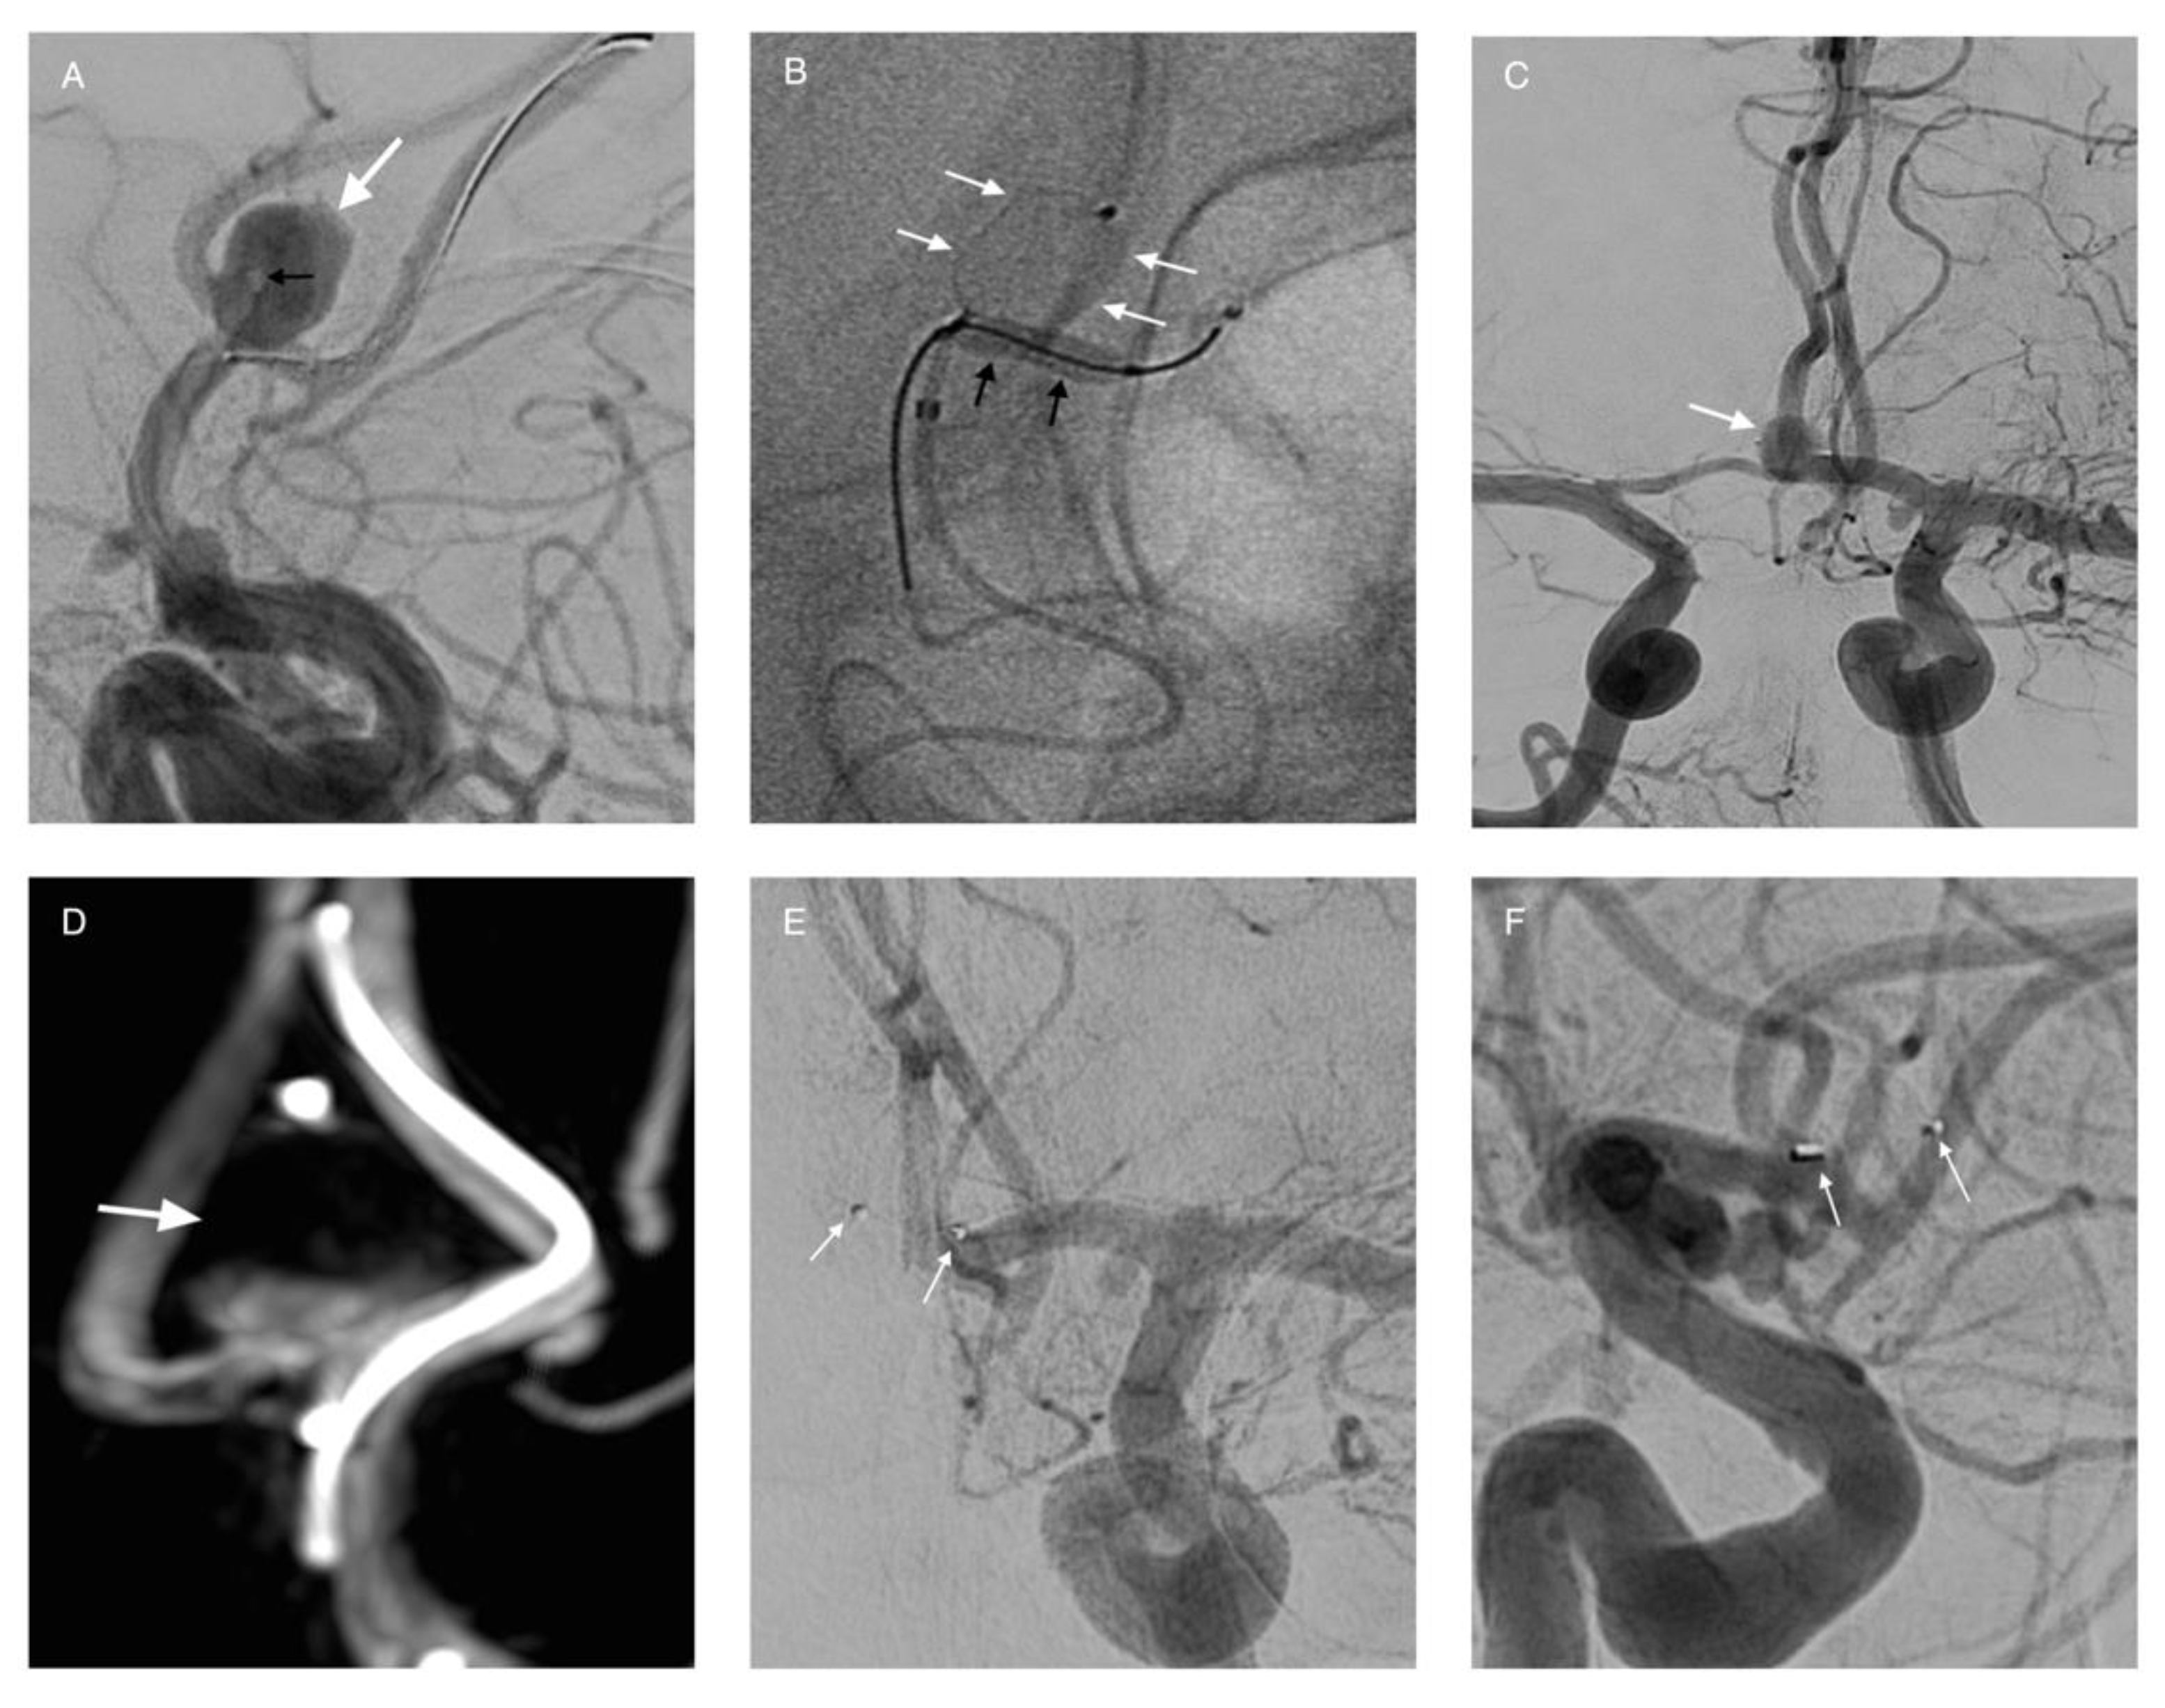

3.6. Intrasaccular Flow Disruptors and Woven Endoluminal Bridge (WEB)